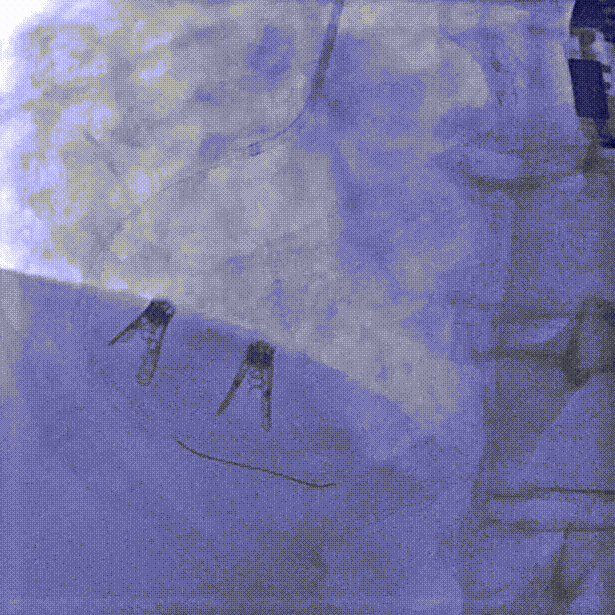

4.打开夹臂调整Orientation后贴靠瓣环。

打开夹臂后调整轴向并贴靠瓣环